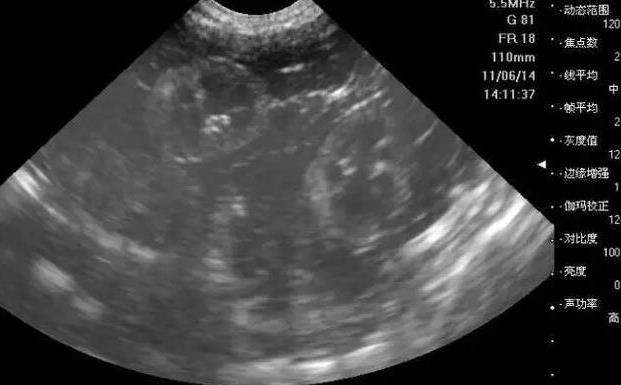

厦门安宝医院试管流程中接下来要做的就是把卵子给取出来,然后完成体外受精,医生会在B超的引导下用特殊的取卵针经过阴道穿刺成熟的卵泡,然后把卵子给取出来,把卵子取出来的同时是在静脉麻醉下进行的,因为大多数的女性可能并不会感染穿刺过程中所导致的痛苦,而体外受精也是非常重要的,精液,经过特殊的洗涤之后,完全可以把精子和卵子放在特殊的培养基当中,这就是所谓的常规受精方式。